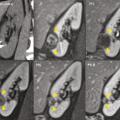

Cryothérapie sous anesthésie locale des tumeurs rénales

Publié le 20 Janvier 2018 || La Revue du Praticien || 68(1):45-7

L’incidence du cancer du rein localisé et de petite taille est en permanente augmentation depuis plusieurs décennies. Cela s’explique en partie par l’essor de l’imagerie médicale puisque plus des deux tiers des cancers du rein sont découverts fortuitement au cours d’un examen d’ima- gerie réalisé pour une autre raison.1, 2 Le…